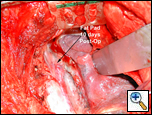

The fat pad is also useful in protecting bronchial suture/staple lines in patients who have undergone

| Figure 2: Buttress of esophageal suture line. |

neoadjuvant chemoradiation or have had previous radiation to the bronchus, and in patients who will undergo postoperative radiation of the mediastinum [3]. Lastly, esophageal suture lines may be buttressed using a pericardial fat pad flap (Figure 2).